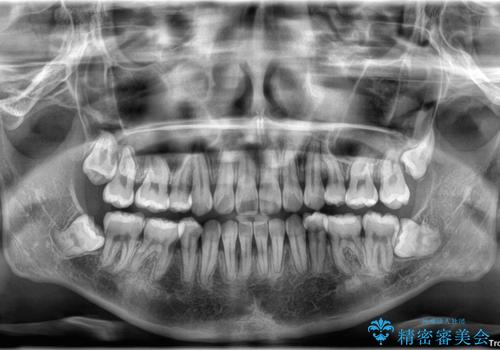

右側上下と左上の小臼歯が一本ずつ少なく、さらに骨格的な左右差もあり上下の真ん中の位置がずれています。

下顎のデコボコの解消と、真ん中の位置を改善するために左下の小臼歯を抜歯することとしました。

また、開咬を改善するため臼歯部にアンカースクリューを用いて圧下する力をかけていきました。

舌のトレーニングは継続して行ってもらっているため、開咬や抜歯したスペースの後戻りはなく、経過は良好です。